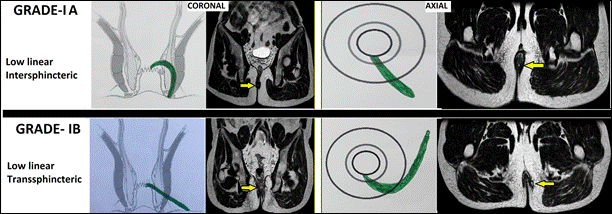

I |

Rò thấp dạng đường thẳng ở khoang gian cơ thắt hoặc xuyên cơ thắt ngoài (liên quan < 1/3 chiều cao cơ thắt ngoài) I-A:Rò thấp dạng đường thẳng gian cơ thắt I-B:Rò thấp dạng đường thẳng xuyên cơ thắt ngoài |